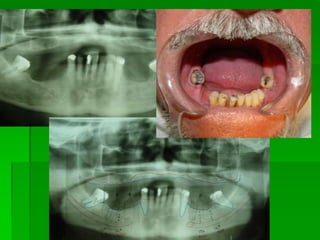

PLANEJAMENTO CIRÚRGICOEXAMES POR IMAGENS:Radiografia Panorâmica para implantes

Avaliação Clínica no Momento da Instalação do ImplanteAparelhos especiais Osstell (mede por freqüência e ressonância)Avaliação Clínica (estabilidade)Torquímetro (mínimo 45 Newtons)Avaliação   radiográfica   ( durante   a instalação,  mede  a  distância   entre implantes e estruturas adjacentes)

Avaliação Clínica Após Período de Osseointegração Imobilidade ClínicaAssintomáticoAusência de imagem radiolúcida peri-implantarAusência de neuropatiaPerda óssea vertical inferior a 1,0 mm após o primeiro ano em  função, e  de   0,1 mm nos anos seguintes